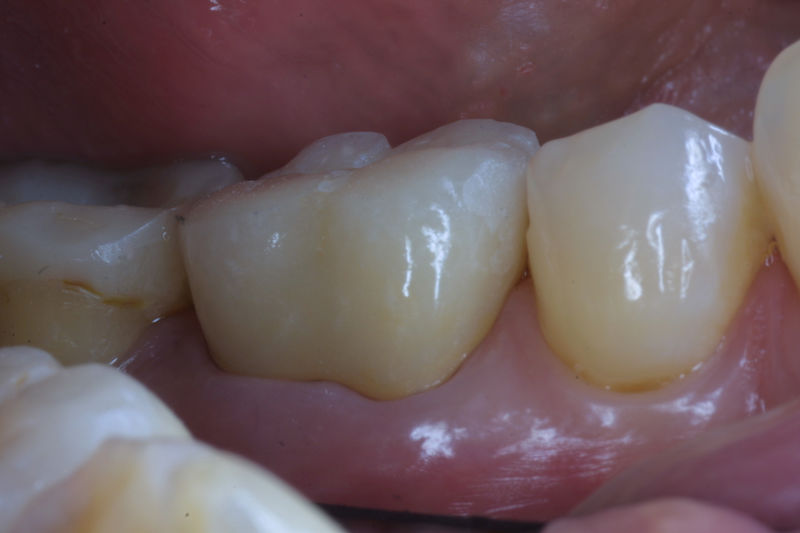

Restauraciones fabricadas en el laboratorio con materiales estéticos, los cuales cubren de manera total dientes anteriores y posteriores. Se utilizan primariamente para restaurar dientes con caries, fracturas y/o defectos amplios, así como soportes de puentes. Para poder enviar el caso al laboratorio se toman impresiones utilizando materiales de impresión o técnicas modernas digitales.

La restauración de un diente tras una endodoncia, es crucial para su supervivencia a largo plazo, ya que el procedimiento puede debilitar la estructura dental. El tipo de restauración elegido depende principalmente de la cantidad de estructura dental remanente después de la endodoncia. Principalmente se usan incrustaciones, coronas y/o postes.